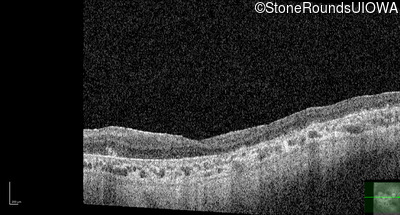

Age at visit: 30 years

OD OS

This 30 year old woman first experienced a reduction of visual acuity at age 20. She had no difficulties in dim light at that time. Over the next 10 years her central vision continued to worsen and she developed some difficulty seeing in dim light.

Age at visit: 34 years